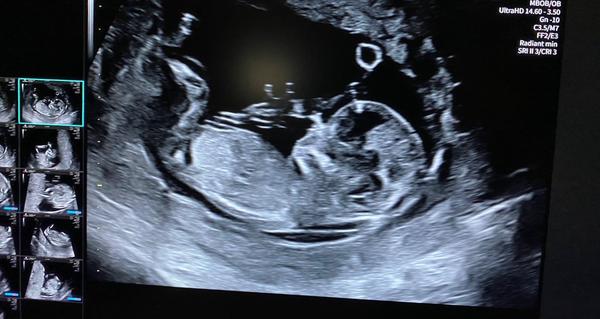

13. týden a pohlaví miminka. Je to chlapeček nebo holčička?

Krásný den, myslite, ze je to spis chlapeček nebo holčička?🙂 Dekuju🙂

Jestli to, co tam jde vidět je opravdu hrbolek, vypadá to podle úhlu n kluka. Ideální záběr to ale není. Zkus na FB nub theory.

Z ty fotky se to nepozná, vždyť tam není videt pohlavní hrbolek, je přes něj noha.

Jestli vidím správně, pohlavní hrbolek směřuje rovně, což by odpovídalo holčičce 😊